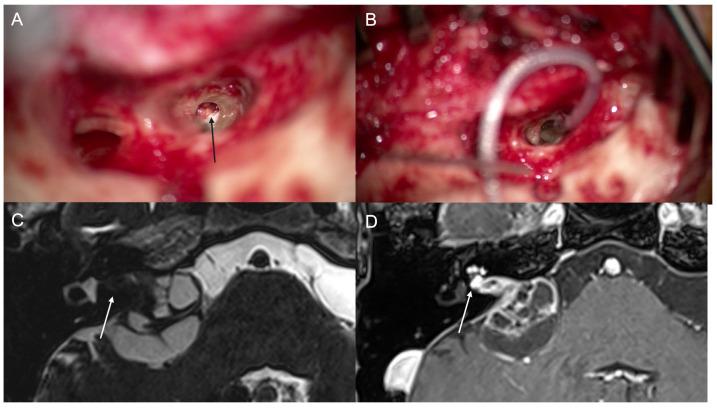

: Simultaneous removal and cochlear implantation (CI) have been reported in intralabyrinthine and intracochlear schwannoma. A wide range of postoperative hearing outcomes have been reported after CI in these cases. This study evaluated the outcomes of performing a simultaneous resection of Schwannoma in cochlea and cochlear implantation (CI), aiming to assess the effectiveness of this combined surgical approach for hearing rehabilitation with CI. : This retrospective case series was conducted at a tertiary care center. The study included four consecutive patients with profound sensorineural hearing loss due to a mass inside the cochlea. These patients underwent simultaneous single-sided CI and tumor resection performed by the same surgeon. Preoperative and postoperative audiological assessments were conducted to evaluate the patients' hearing outcomes before and after the surgical intervention. : Simultaneous CI with tumor resection was successful in all cases. Two of the four patients had a unilateral tumor, while the other two had a bilateral tumor with the involvement of the internal auditory canal and cerebellopontine angle (neurofibromatosis type 2 (NF2)). In two cases of unilateral tumor, aided free-field pure tone average (PTA) was 26 dB, and 46 dB hearing level (HL), and word recognition score (WRS) at 65 dB was 40% and 68%, respectively, 3 months after surgery. In two cases of tumor with NF2, aided free-field PTA was 36 dB and 60 dB HL, and both cases showed 0% WRS at 65 dB 3 months after surgery. : Simultaneous schwannoma excision and CI in patients with Schwannoma inside cochlea are surgically practical and safe. Postoperatively, there was a notable improvement in hearing in cases of sporadic schwannoma, regardless of the type of CI used. However, there was 0% WRS in the two NF2 patients with a mass in the internal auditory canal.

: 据报道,在迷路内和耳蜗内神经鞘瘤中可同时进行肿瘤切除和人工耳蜗植入(CI)。这些病例中,CI术后的听力结果范围广泛。本研究评估了同时切除耳蜗神经鞘瘤和人工耳蜗植入(CI)的结果,旨在评估这种联合手术方法对CI听力康复的有效性。: 本回顾性病例系列研究在一家三级医疗中心进行。该研究纳入了4例因耳蜗内肿物导致重度感音神经性听力损失的连续患者。这些患者由同一位外科医生同时进行了单侧CI和肿瘤切除。术前和术后进行了听力学评估,以评估手术干预前后患者的听力结果。: 所有病例中同时进行CI和肿瘤切除均成功。4例患者中有2例为单侧肿瘤,另外2例为双侧肿瘤,累及内耳道和桥小脑角(2型神经纤维瘤病(NF2))。在2例单侧肿瘤病例中,术后3个月时,助听自由声场纯音平均听阈(PTA)分别为26 dB和46 dB听力级(HL),65 dB时的言语识别得分(WRS)分别为40%和68%。在2例NF2肿瘤病例中,助听自由声场PTA分别为36 dB和60 dB HL,术后3个月时,2例患者在65 dB时的WRS均为0%。: 对于耳蜗内有神经鞘瘤的患者,同时切除神经鞘瘤和CI在手术上是可行且安全的。术后,散发性神经鞘瘤病例的听力有显著改善,无论使用何种类型的CI。然而,2例内耳道有肿物的NF2患者的WRS为0%。